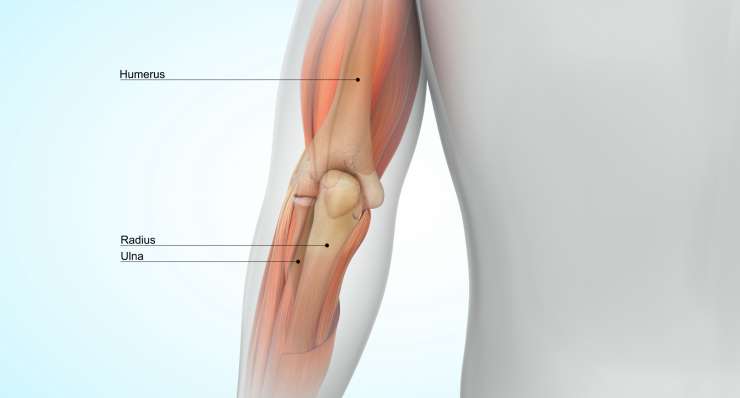

Основные направления лечения в хирургии локтя

артроз локтя

Артроз локтевого сустава, то есть износ суставного хряща, сначала лечится профессором, доктором медицины Франком Мартешлегером консервативными методами, а при запущенной стадии — артроскопически или с помощью современных протезов локтевого сустава.

перелом локтя

В зависимости от типа травмы, профессор, доктор медицины Франк Мартечшлегер лечит перелом локтя консервативно или хирургически с помощью точных методов остеосинтеза, чтобы полностью восстановить стабильность и подвижность сустава.

нестабильность локтя

Нестабильность локтя, чаще всего являющаяся следствием повреждения связок или капсулы после падения, лечится профессором, доктором медицины Франком Мартечшлеггером в зависимости от степени тяжести консервативно или путем оперативной реконструкции стабилизирующих структур.

Лечение локтей в Мюнхене

В области хирургии локтя профессор Франк Мартешлегер (Frank Martetschläger) в Мюнхене предлагает широкий спектр современных методов диагностики и лечения. К ним относятся артроз локтя, нестабильность локтя, эпикондилит (теннисный и гольф-локоть), переломы локтя, а также хронические воспаления или ограничения подвижности. В зависимости от результатов обследования лечение проводится консервативно — например, с помощью физиотерапии, инъекций или ударно-волновой терапии — или хирургически, в большинстве случаев с помощью минимально инвазивной артроскопической техники. При сложных травмах могут потребоваться открытые вмешательства и реконструктивные операции для восстановления функции и стабильности сустава. Пациенты в Мюнхене получают преимущества точной диагностики, комплексного подхода к лечению и опыта международно признанного специалиста по локтевому суставу.